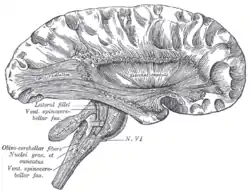

![]() Deep dissection of cortex and brain-stem. (External capsule visible at center.) | |

The external capsule is a series of white matter fiber tracts in the brain. These fibers run between the most lateral (toward the side of the head) segment of the lentiform nucleus (more specifically the putamen) and the claustrum.

The white matter of the external capsule contains fibers known as corticocortical association fibers. These fibers are responsible for connecting the cerebral cortex to another cortical area. The capsule itself appears as a thin white sheet of white matter.[1]

The putamen separates the external capsule from the internal capsule medially and the claustrum separates it from the extreme capsule laterally. But the external capsule eventually joins the internal capsule around the lentiform nucleus.